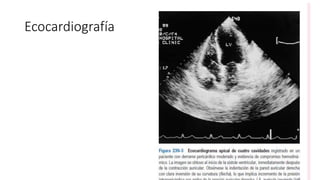

Ecocardiografía

• En la ecocardiografía

• se observó severo derrame pericárdico, sin bandas de fibrina ni masas

intrapericárdicas, murales o intracavitarias;

• colapso de la aurícula y el ventrículo derechos en diástole y cambios

acentuados de la velocidad del flujo diastólico mitral con la respiración.